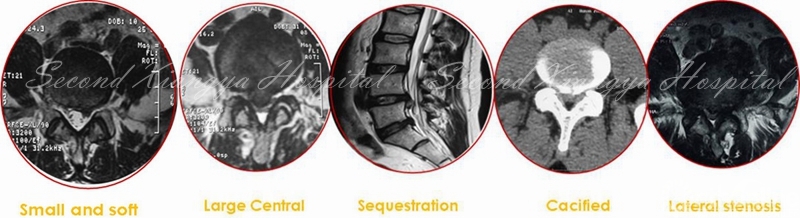

随着经皮内镜技术的进步,其适应症已由单纯的软性突出拓展到处理骨性椎管狭窄和复杂退行性疾患,即由“欺软怕硬”,到“软硬兼吃”。内镜技术已经涵盖了腰椎、颈椎和胸椎退行疾患范畴。然而,由于存在陡峭的学习曲线,为规避风险,增加疗效,树立信心,初期开展应循序渐进,忌超技术能力的盲目应用。

经皮内窥镜在腰椎应用由椎间孔和椎板间两种入路,目前影响入路的选择的因素较多,包括病理因素、患者因素,也有医生的因素,入路选择既有最佳适应症,也有相对适应范围。

总体来讲,在L5/S1节段,除椎间孔髓核突出外,多数病例建议采用椎板间入路,操作更为容易简捷。对于L4/5以上节段的退行性病变,椎板间入路适合髓核游离、腋下型、较大钙化偏中央、中央或侧隐窝骨性狭窄,以及神经背侧受压为主的病例,对于椎间孔区域的髓核突出(上不超过椎弓下缘,下位于椎弓根中份)、侧隐窝狭窄,神经根腹侧压迫为主的患者,椎间孔入路是较佳选择。如果同时合并椎间孔狭窄或侧隐窝狭窄,可以采用椎板间和椎间孔联合入路。无论采取何种入路,都需要在减少付损伤同时获得充分减压,已到达兼顾微创和治疗的双重目的。

经皮内窥镜在颈椎中的应用,有后路经椎间孔入路,前路经椎间隙和椎体两种入路。后路经椎间孔入路的适用范围主要包括C3-7神经根型颈椎病、颈椎间孔骨性狭窄,亦有部分颈椎管局限性狭窄患者可以采取后路内镜下椎管减压的手术方式。前路经椎间隙适合中央型髓核突出,经椎体用于髓核脱垂类型,不适合颈椎不稳、成角、钙化、间隙高度<4mm和严重压迫者。